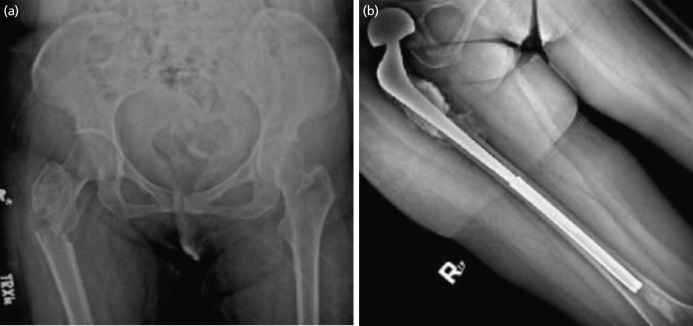

Introduction: The proximal femur is the most common long bone affected by metastatic disease. Pathologic fractures in this area are frequent, secondary to weight-bearing and deforming forces. Long-stem endoprosthetic replacement is often used to replace and bypass segments affected by metastases. However, implant cost remains prohibitive for patients in low-resource settings. An improvised megaprosthesis using a hip implant combined with Kuntscher nail provides an economic option.

Material and methods: This is a case series of three patients diagnosed with pathologic fracture of the hip secondary to metastatic bone disease who underwent proximal femoral resection with reconstruction using an improvised endoprosthesis in a single tertiary hospital. Outcomes determined include total blood loss, total surgical time, length of hospital stay, latest functional score using the Musculoskeletal Tumour Society (MSTS) score, and pain scale using the numerical rating scale (NRS).

Results: For case 1, a 42-year-old female with metastatic breast carcinoma, currently alive with disease and able to perform activities of daily living (ADLs) with minimal assistance; for case 2, a 77-year-old male diagnosed with prostatic carcinoma, able to ambulate with assistive device before expiring 2 years post-surgery; and for case 3, a 57-year-old female with metastatic breast carcinoma, able to resume unassisted ADLs at 3 months post-surgery before refusing systemic treatment in her second year of surveillance monitoring.